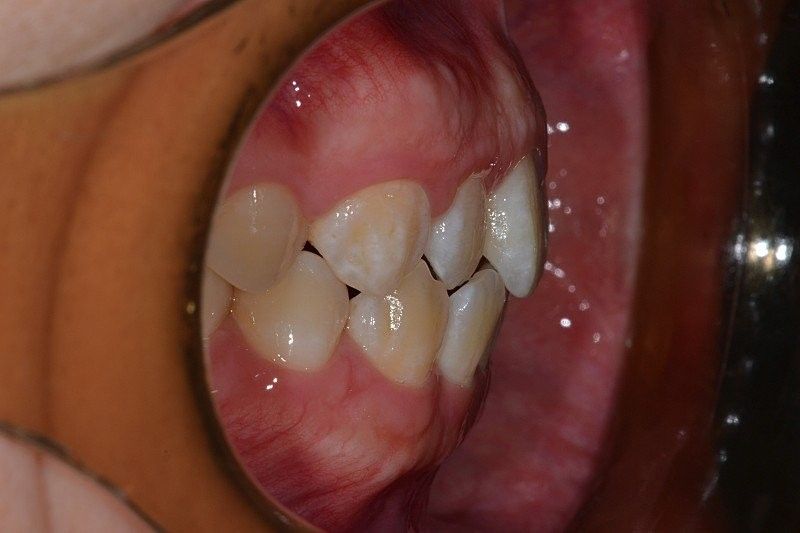

아랫치아 잇몸이 볼록 나와보이는 것 같아보입니다

보이는 부분에 있어서는 정상각도에서 크게 벗어나지는 않으나 이는 전방위적인 평가 및 골격과 함께 평가를 해보아야 합니다. 지금 상태로 보았을 때는 교정을 해서 치축을 돌려야할 만큼의 문제는 아니며 일반 사람들이라면 평생 교정을 하지 않고 살아가는 분들도 많습니다.

단순 임상사진과 cephalo만 봐서는 정확히는 알 수 없으나 교정치과에서 제대로 한 치료라면 문제 없을 것으로 사료됩니다.